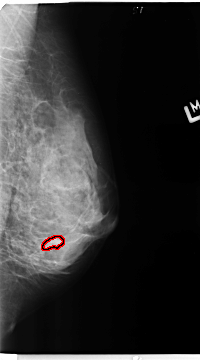

B_3359_1.LEFT_MLO

LEFT_MLO LINES 4680 PIXELS_PER_LINE 2600 BITS_PER_PIXEL 12 RESOLUTION 50 OVERLAY

FILE: B_3359_1.LEFT_MLO.OVERLAY

TOTAL_ABNORMALITIES 1

ABNORMALITY 1

LESION_TYPE MASS SHAPE IRREGULAR MARGINS CIRCUMSCRIBED-OBSCURED

ASSESSMENT 4

SUBTLETY 3

PATHOLOGY BENIGN

TOTAL_OUTLINES 1

BOUNDARY